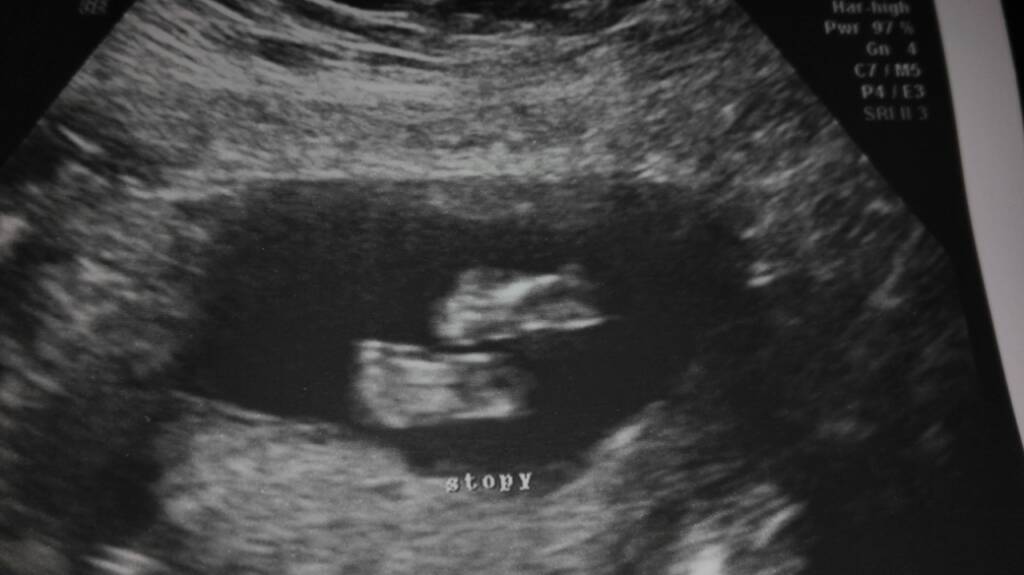

Otyłość w ciąży

Colorado [emoji110][emoji110][emoji110]